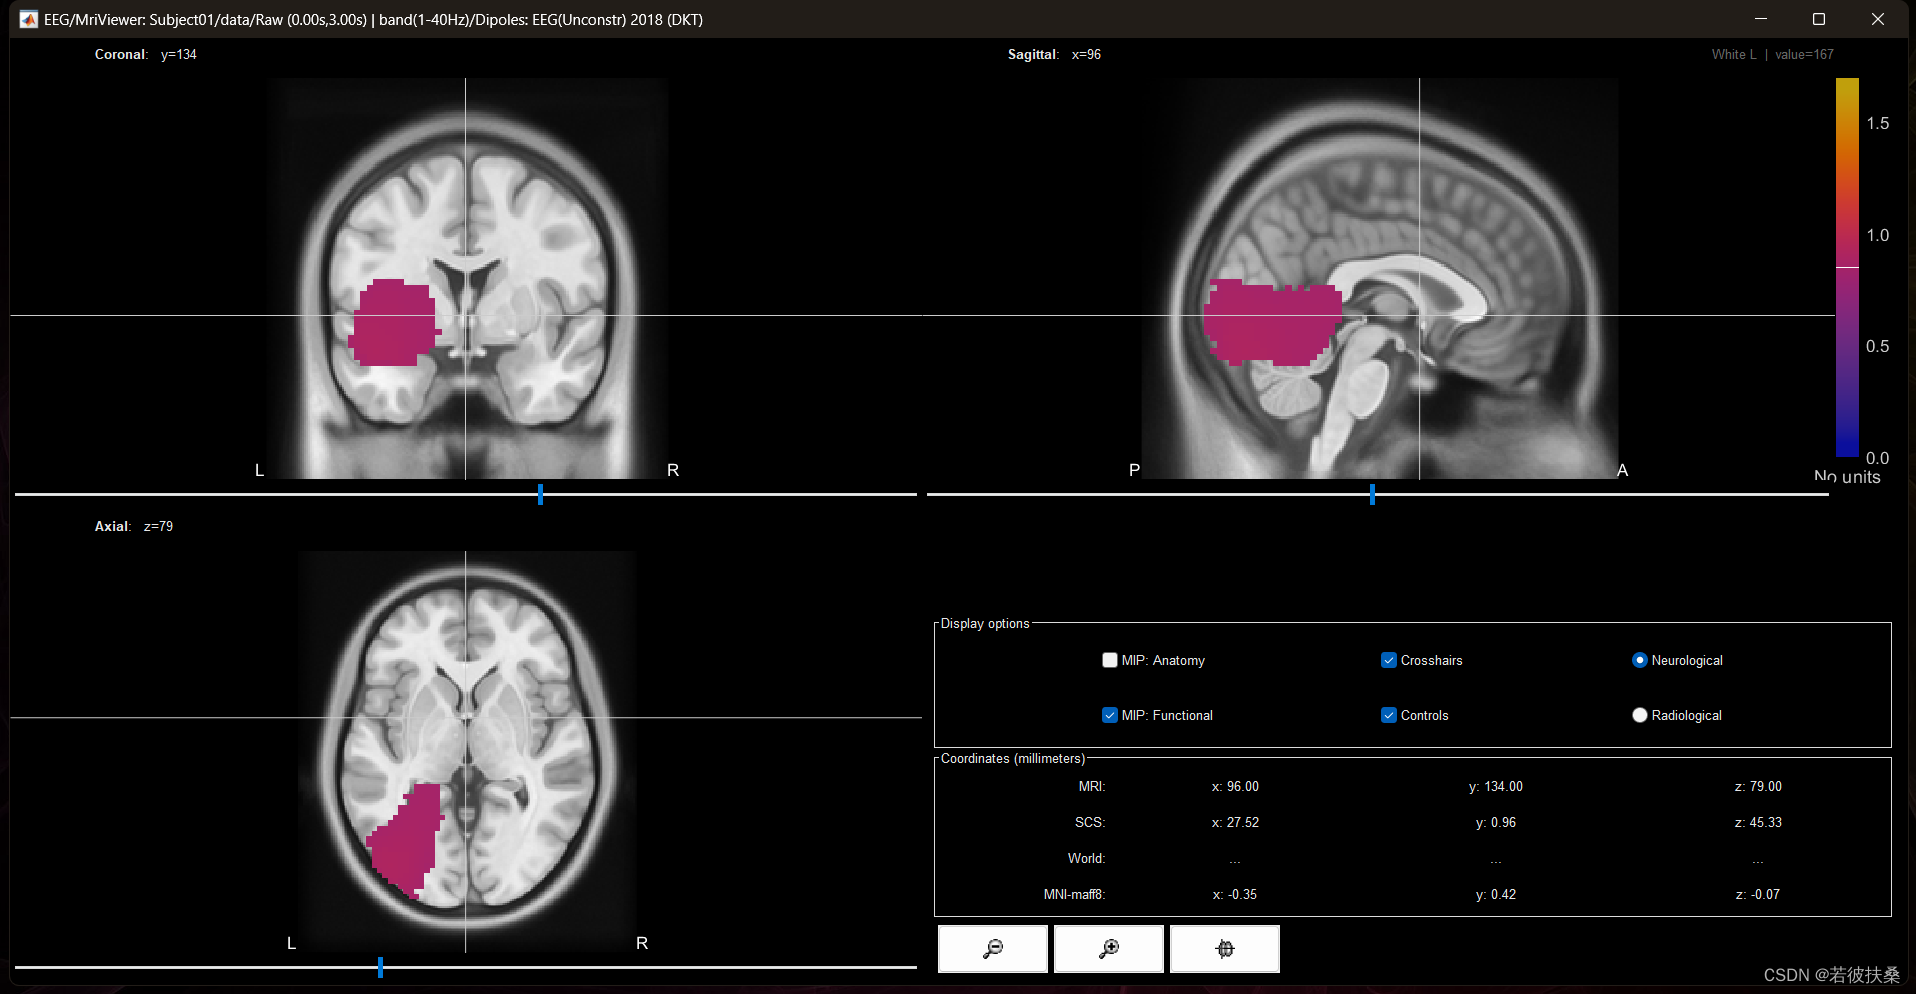

6. 源估计

Brainstorm使用模板进行源分析的标准流程为:脑电电极定位->计算头模->源估计->源分析

6.3 源估计

右键选择处理后的Raw文件,选择Compute sources

设置如下:

点击OK即可。 之后会在Raw下方出现如下文件

双击该文件即可弹出 皮层模型

再右键点击选择 EEG Recordings即可弹出曲线

源模型是显示某一个时间点或(某段时间的平均值)的神经活动,拖动曲线下方的红色控件,即可查看不同时间点的时间活动情况。

至此,我们已经完成EEG的源定位,并且获得了一张皮层脑电图,后续作者将会具体讲述如何进行手动ICA去伪迹、以及如何进行源分析。